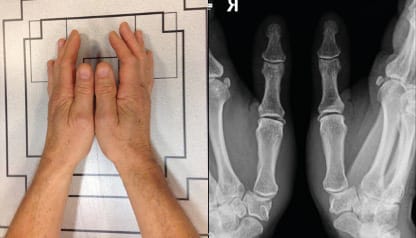

The standard frontal and lateral projections required to achieve good visualisation of the joint have been thoroughly described by Kapandji [9], Kapandji AI, Moatti E, Raab C. La radiographie spécifique de l’articulation trapézo-métacarpienne. Sa technique, son intérêt. Ann Chir Main 1980;34:719-26.[10] Kapandji TG, Kapandji AI. Nouvelles données radiologique sur la trapézo-métacarpienne. Résultats sur 330 dossiers. Ann Chir Main 1993, 12 , N°4, 263-274 and these are still an excellent reference. A posteroanterior projection (Figure 1) is used for the frontal view otherwise the metacarpophalangeal and interphalangeal joints would be visualised first (Figure 1). The lateral view is achieved through an ulnar to radial projection (Figure 2). Across the Atlantic, variations to these projections exist and some useful additions are made. Robert’s view [11] Robert P. La radiographie de l’articulation trapézo-métacarpienne. Les arthroses de cette jointure. Bulletins et mémoires de la Société de Radiologie Médicale de France. 1936;24:687-90. is a variant of the Kapandji frontal view that uses an AP rather than PA projection and is very popular in the English-speaking world. We should not forget comparative images, such as the Eaton view with and without stress. To assess the triscaphoid it is important to include Gedda’s view [12] Gedda KO (1954). Studies on Bennett’s fracture: anatomy, roentgenology and therapy. Acta Chirurgica Scandinavica, 193(Suppl): 1. , also known as Bett’s view [13] Taleisnik J. The Wrist, 1st edn. New York, Churchill Livingstone, 1985: 95–96. , among dynamic views in ulnar and radial deviation. We will move on to a detailed discussion of the key views and their positioning.

Frontal views : This radiography is performed using dorsopalmar and lateral projections. For the frontal view it is crucial for the sesamoids to project over the first metacarpal head. (Figure 1). These frontal images clearly show the IP and thumb MCP joint spaces. The TMC joint space, however, cannot be visualised simultaneously.

Lateral views : These are carried out in the exact same way as Kapandji’s lateral views: it is key to make sure the sesamoids are superimposed on lateral views as this will demonstrate the concave base of the first metacarpal and the convexity of the trapezium while enabling the base of the second metacarpal to be slightly superimposed. (Figure 2) This view allows for a very good appreciation of the involvement of the MCP and IP joints.